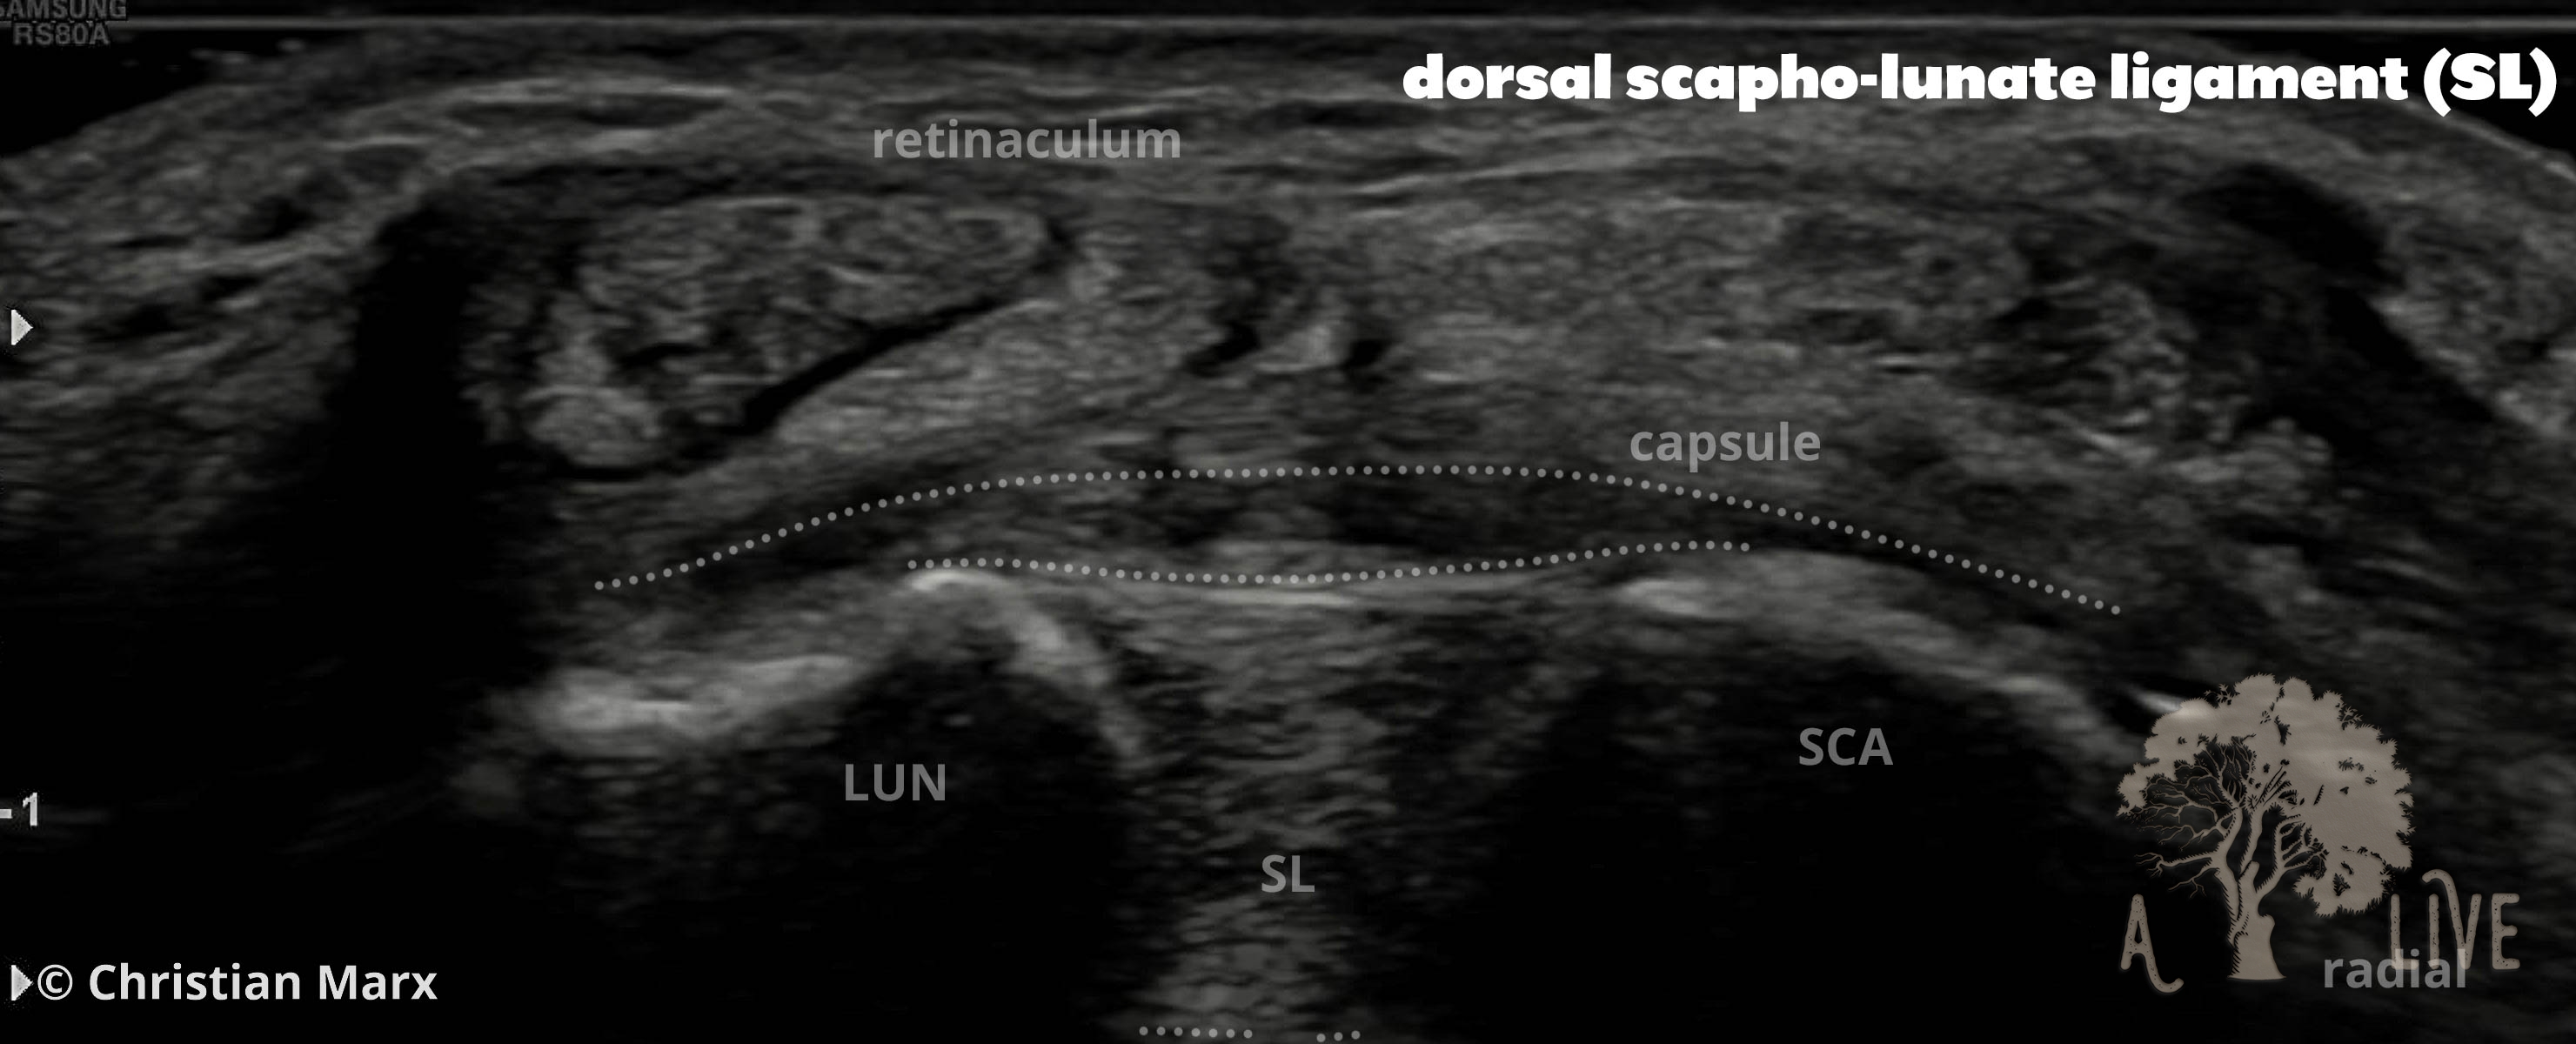

carpal ligaments